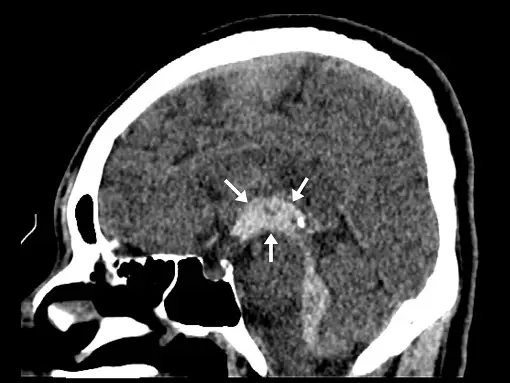

34.患者有腦室內出血(intraventricular hemorrhage, IVH),矢狀面重組的(sagittal reformatted)電腦斷層影像如下圖,箭號所指異常處是什麼構造?

- 這是一張無顯影劑的頭部 CT 矢狀面重組影像(non-contrast sagittal reformatted CT)。

- 圖中可見腦室系統內有明顯的高衰減(hyperdense,呈現白色)區域,代表急性出血(acute hemorrhage)。

- 箭號所指的白色高密度區域位於大腦正中切面(mid-sagittal)的中心位置。從解剖邊界來判斷:該構造位於穹窿(fornix)與間腦(diencephalon)之間,其後下端呈現漏斗狀向下延伸,連通至中腦導水管(cerebral aqueduct; aqueduct of Sylvius)。

- 這個完全被急性血液鑄型填滿的空腔即為「第三腦室」。此外,仔細觀察影像,還可見高密度的血液沿著中腦導水管向下流注至第四腦室。